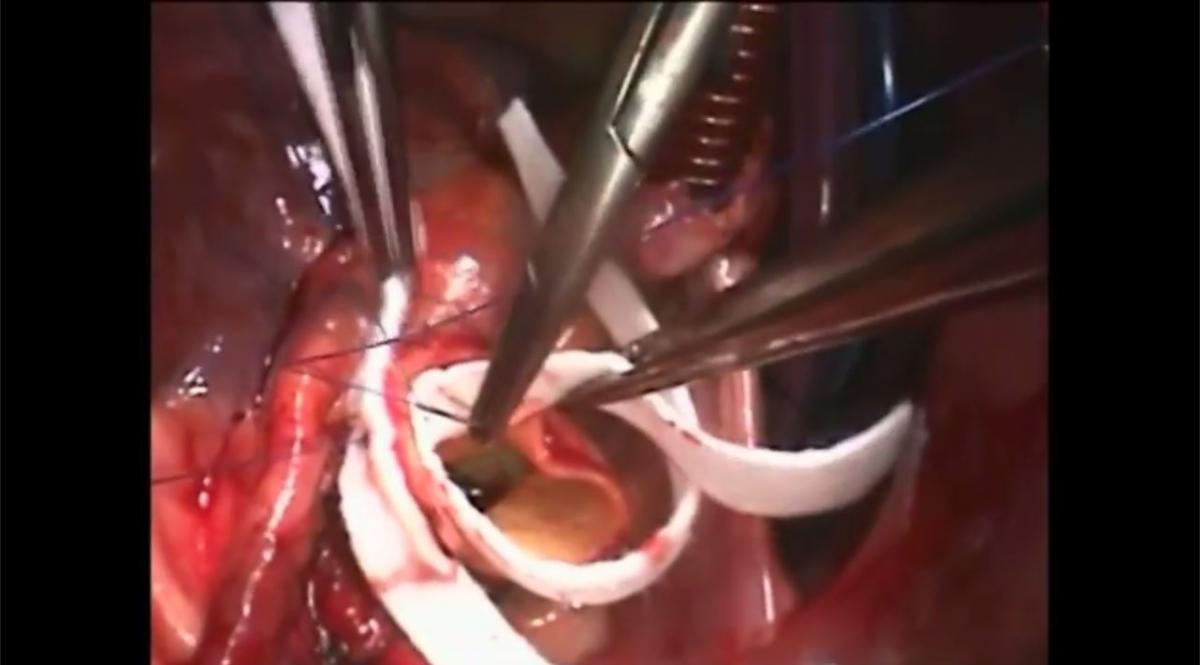

4. Trans-Aortic Valve Replacement with Edwards Sapien-Ascendra 3 Mark Russo Paolo Tartara |